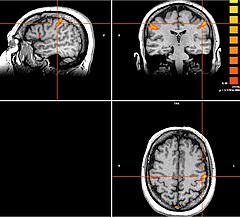

Neben den Bewegungsstörungen sind mittlerweile auch einige neuropsychiatrische Erkrankungen, wie die Depression oder Zwangsstörungen bekannt, bei denen fehlerhafte Hirnareale durch die Tiefe Hirnstimulation verändert (=moduliert) werden können. Bei schweren therapieresistenten Verläufen kann auch hier dieses Verfahren angeboten werden.

Tiefe Hirnstimulation bei psychiatrischen Erkrankungen

Neben den Bewegungsstörungen sind mittlerweile auch einige neuropsychiatrische Erkrankungen, wie die Depression oder Zwangsstörungen bekannt, bei denen fehlerhafte Hirnareale durch die Tiefe Hirnstimulation verändert (=moduliert) werden können. Gemeinsam mit dem ZI Mannheim erforschen wir neue Zielstrukturen und Indikationen.